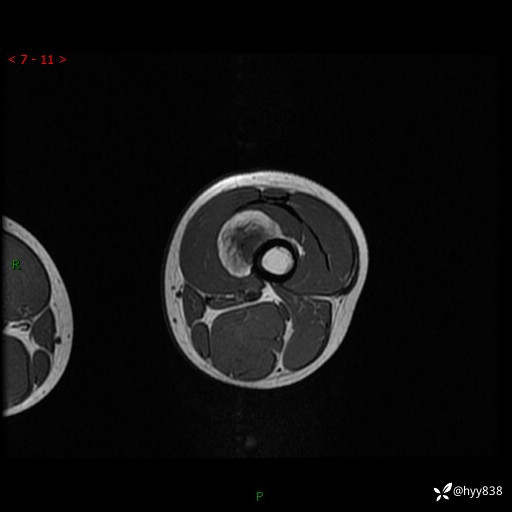

现病史:患儿3天前无意中被发现其左大腿有一包块,约鸡蛋大小,包块表面皮肤无红肿、触痛,无发热、破溃等,患儿家属当时未做特殊处理,经观察发现包块未见消退,今携患儿来我院就诊,门诊医师以“左大腿包块”收入院。 病程中,患儿神清,精神可,饮食睡眠正常,大小便通畅,体力体重无明显改变。

左大腿MRI平扫+增强